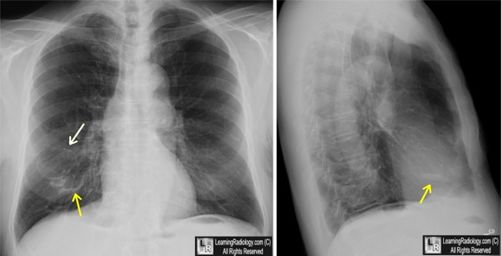

图3 囊状支气管扩张:CT,可见支气管明显扩张,一些可见气-液平面(黄色箭头),大部分位于右肺。胸部X线片:显示右下叶薄壁的囊状影(白色箭头),部分可见气-液平面(黄色箭头)。医脉通编译整理自:http://learningradiology.com/index.htm